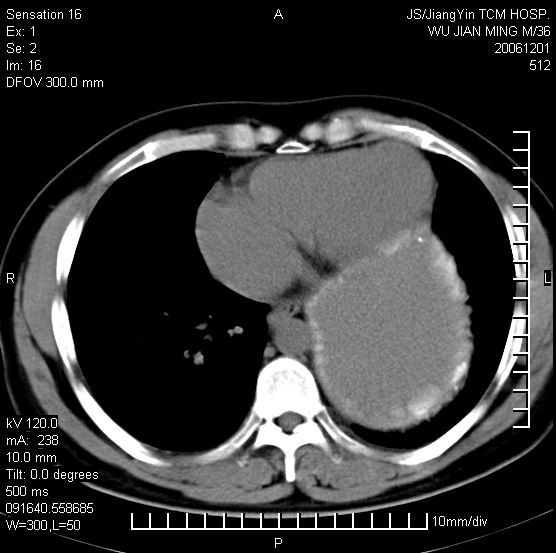

以下是引用dyqct在2006-12-1 21:17:00的发言:[br]左心缘旁及后肋膈窦区见巨大椭圆形混杂密度肿块,周围见大小不等斑片状钙化,内部无强化,周围包膜轻度强化,心脏明显受压变形,即明显占位效应,肿块广基与心包、膈相连。肝、脾内、肝门见多数小结节状钙化影。[br]考虑:1、左心缘旁及后肋膈窦区慢性包裹性胸膜炎(结核性);[br] 2、肝、脾及肝门淋巴结核已钙化。[br]

以下是引用zrs在2006-12-2 17:28:00的发言:[br]肺内、肝脾内虽有钙化,但不支持结核性胸胸膜炎包裹,而支持寄生虫感染![br][br]

以下是引用zyx168在2006-12-2 10:10:00的发言:[br][br]肝脾肺内多发钙化灶